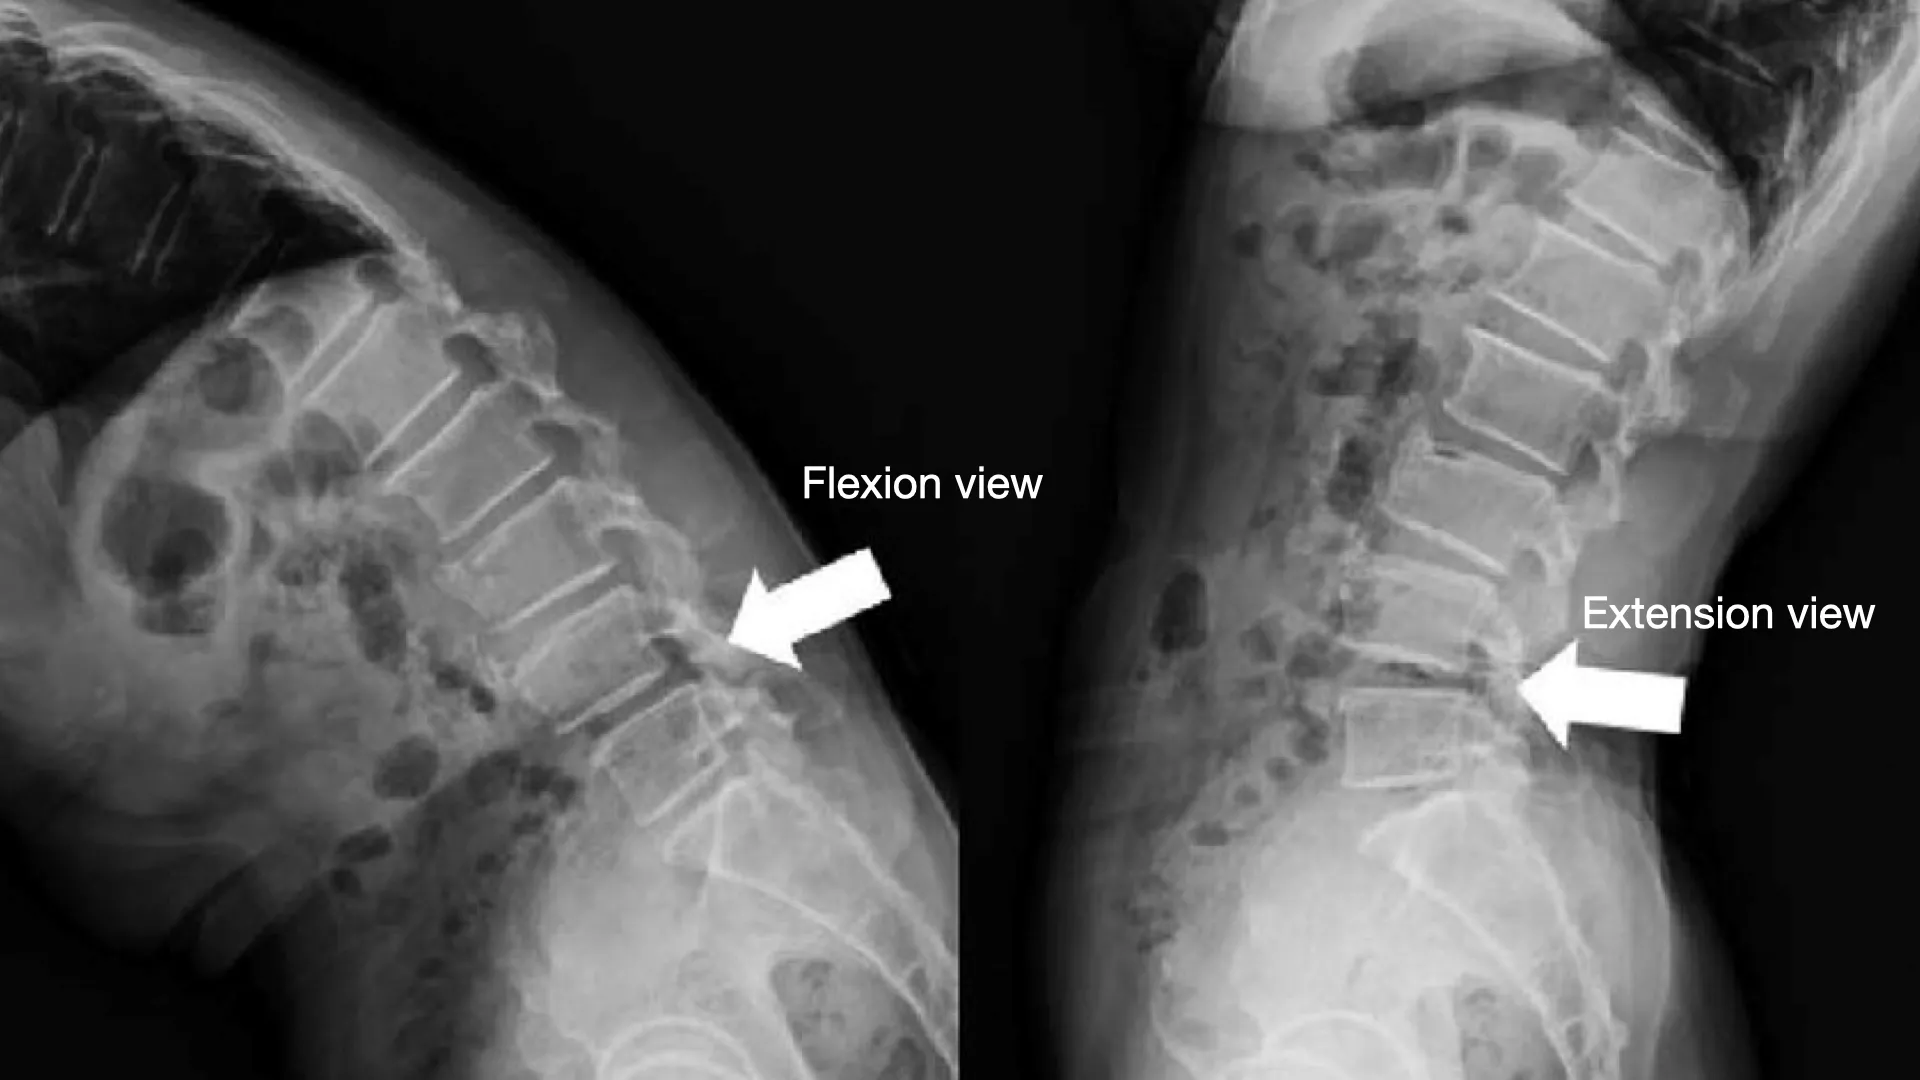

ท่าก้ม-เงย (Flexion-Extension View)

- ลักษณะ: ผู้ป่วยจะยืนในท่าด้านข้าง แล้วถ่ายภาพ 2 ครั้ง โดยครั้งแรกเป็นท่าก้มตัวสุด และครั้งที่สองเป็นท่าเงยตัวสุด

- ความสำคัญ : เป็นท่าที่สำคัญมาก เพราะจะช่วยให้แพทย์เห็น “ความไม่มั่นคง” ของกระดูกสันหลังได้อย่างชัดเจน หากมีภาวะกระดูกสันหลังเคลื่อน การถ่ายภาพในท่านี้จะช่วยยืนยันการวินิจฉัยและวางแผนการรักษาที่แม่นยำยิ่งขึ้น เนื่องจากจะเผยให้เห็นว่าข้อกระดูกมีความผิดปกติในขณะที่มีการเคลื่อนไหวหรือไม่